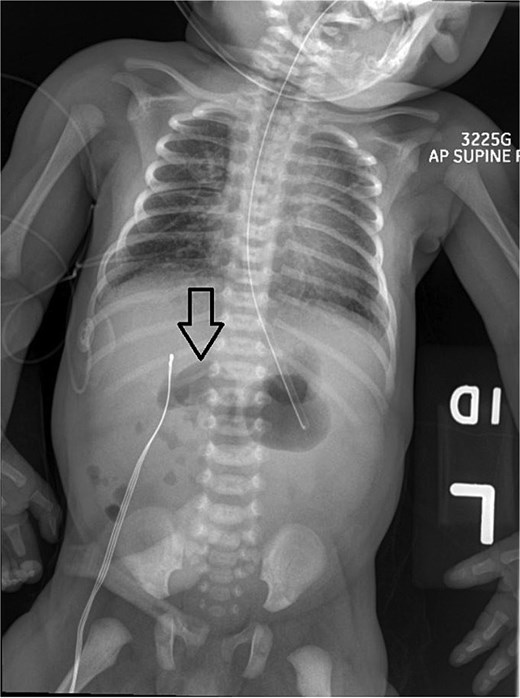

On Day 3 of life, she developed multiple episodes of bilious emesis and passed meconium-stained stools. An abdominal radiograph revealed gas-filled, non-distended bowel loops on the right and absence of small bowel gas on the left (Fig. 1), raising suspicion for malrotation. An upper GI (UGI) series confirmed abnormal duodenal positioning and obstruction, suggestive of malrotation with volvulus (Fig. 2). Emergent Ladd’s procedure was performed, revealing midgut volvulus with cloudy peritoneal fluid but viable bowel.

Initial UGI series demonstrates abnormally dilated descending duodenum with no contrast crossing the midline. Findings are consistent with obstruction.